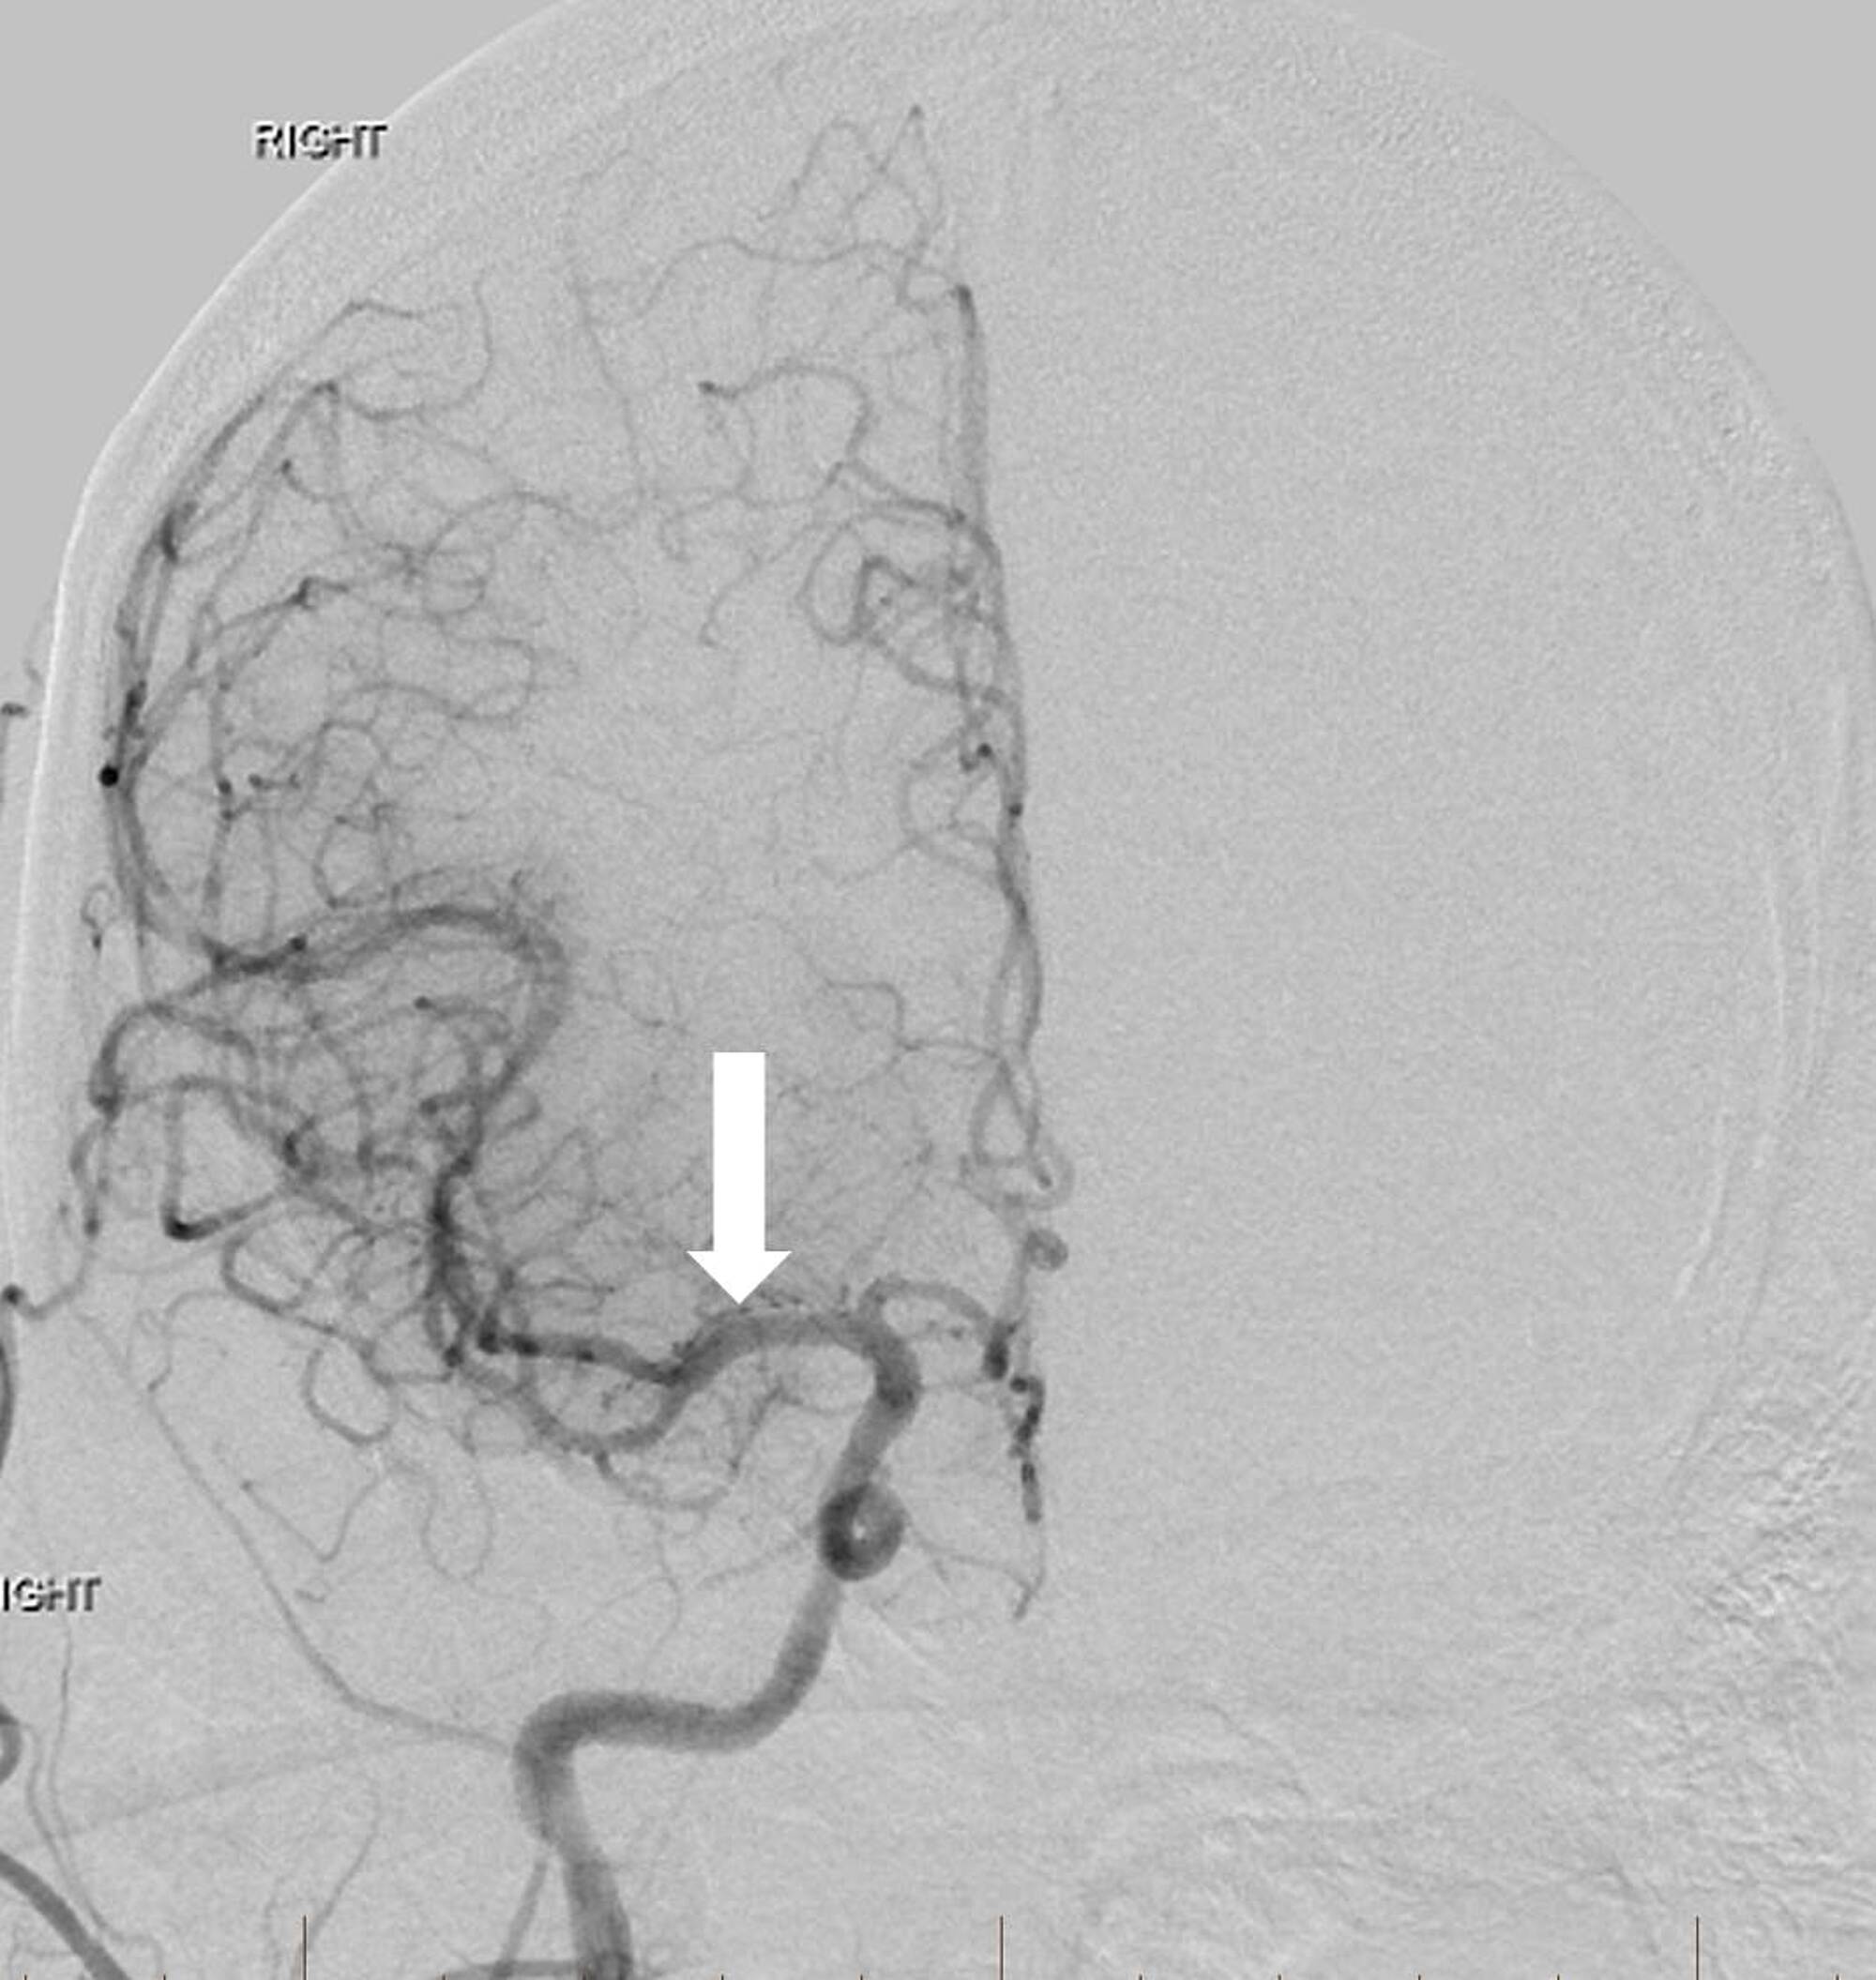

The right MCA was then patent with excellent flow to the anterior circulation (Figure 3).